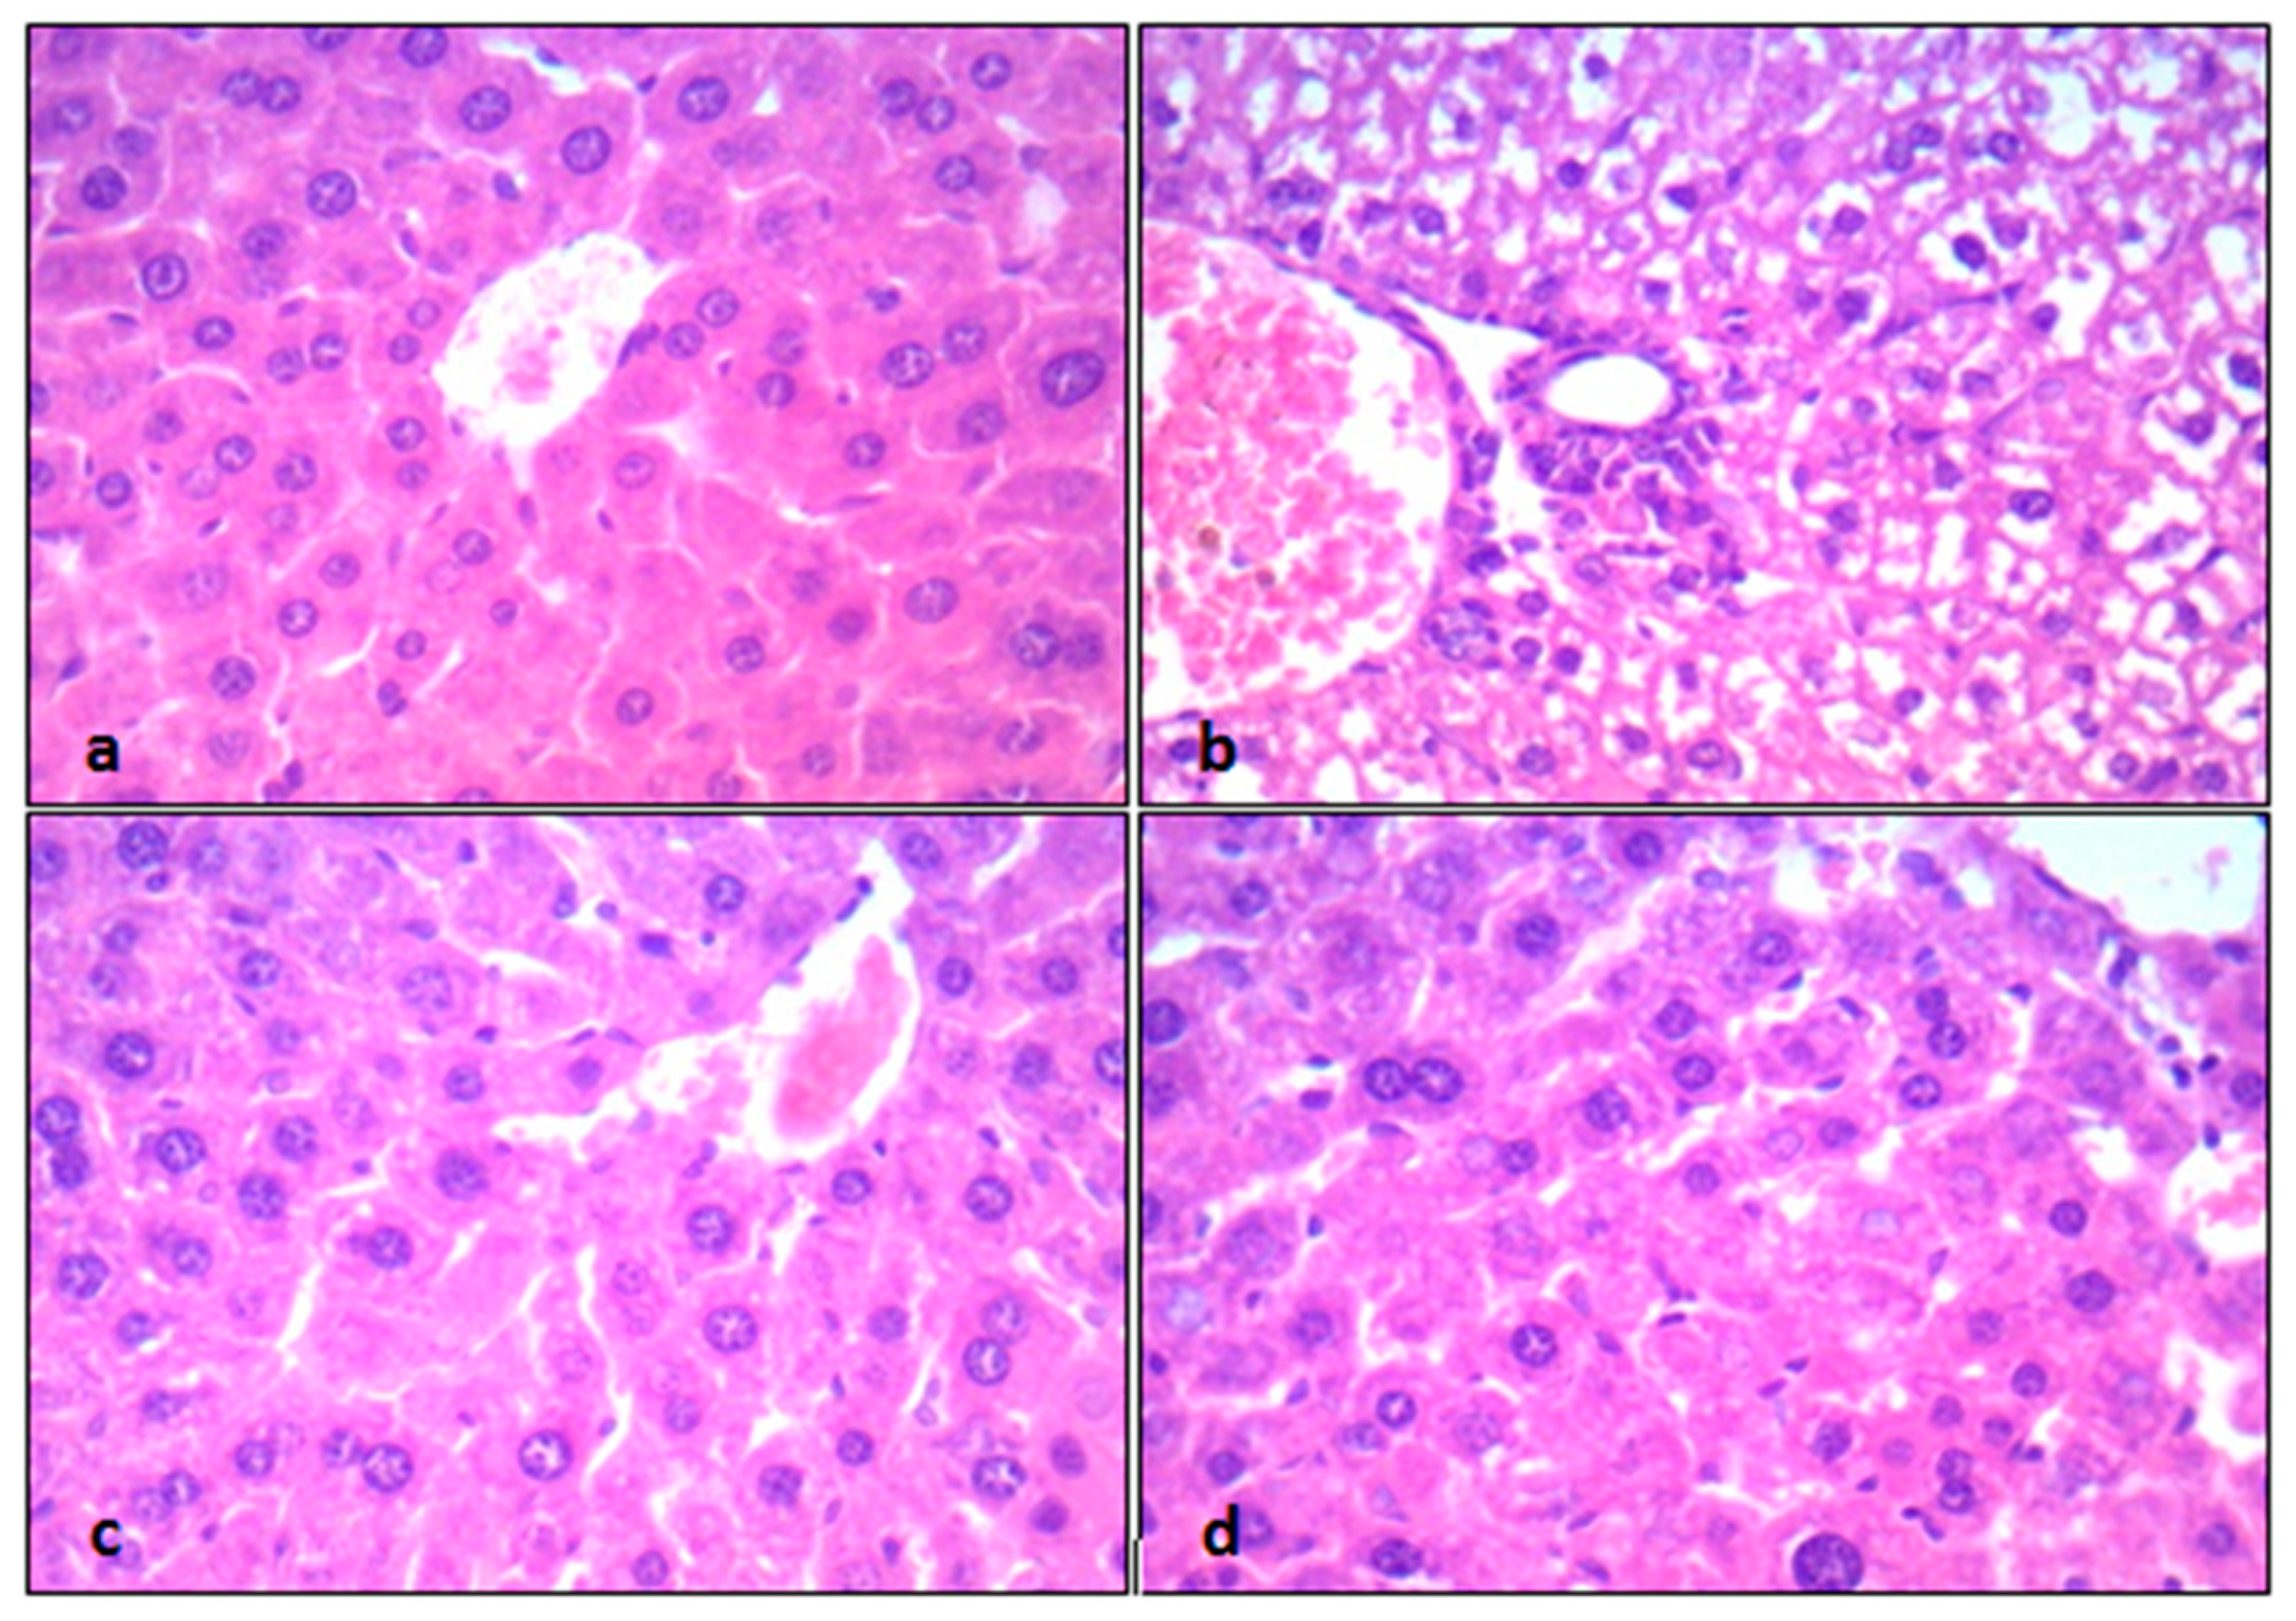

2.4. Histopathological Examination and Analysis

| Groups | Grades | Mean Scoring Grades for Hepatic Histopathological Changes | |||

| 1 | 2 | 3 | 4 | ||

| Control | 7 | 1 | 0 | 0 | 1.125 ± 0.13 |

| CP-intoxicated | 0 | 1 | 4 | 3 | 3.25 ± 0.25 a |

| CP + EPO (5 mg/kg) | 0 | 6 | 1 | 1 | 2.37 ± 0.26 ab |

| CP + EPO (10 mg/kg) | 6 | 1 | 1 | 0 | 1.63 ± 0.42 b |

| (a) | |||||